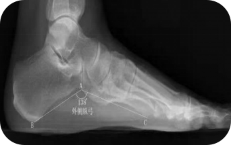

X线测量法:第一跖骨距骨角、距舟覆盖角及跟骨倾斜角等参数的测量,对足进行影像学评估

足负重前后位、足负重侧位(足内弓角测量、外弓角测量、跟骨倾斜角)